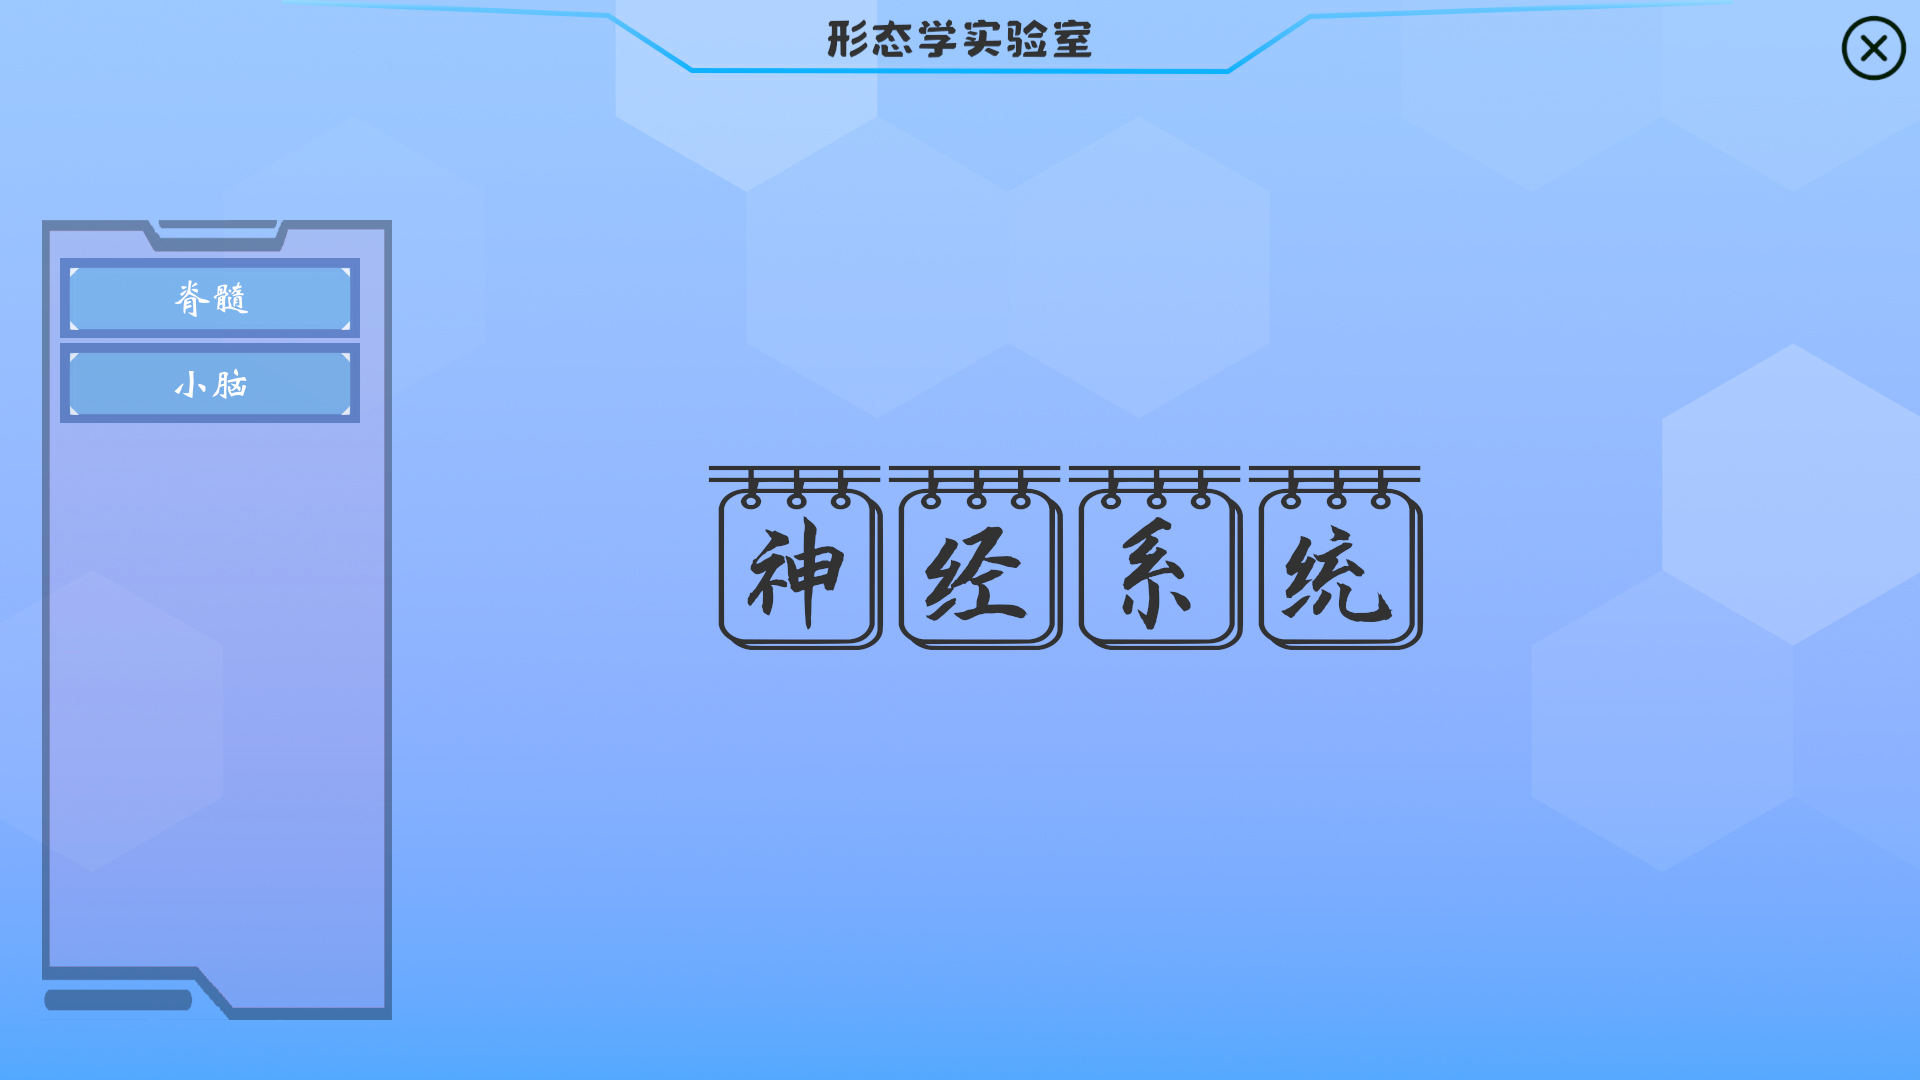

本产品打破以往产品功能单一的局面,目前具有解剖教学、组胚教学、影像教学、模拟介入手术等功能

解剖教学模块内置了人体全骨骼标本,你可以根据系统索引进行学习

影像学模块模拟PAC系统,在这里您可以学习到各种疾病的影像学表现